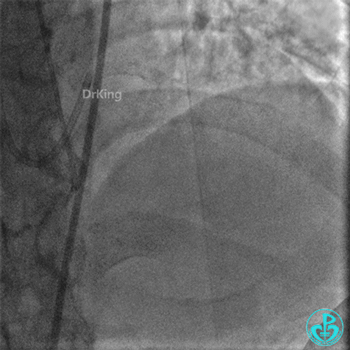

右冠脉支架通畅无狭窄,右冠脉给前降支远端提供逆向侧支循环。

EBU指引导管左冠脉造影显示粗大前降支中段闭塞,闭塞段近端有对角支发出,前降支同侧逆向显影,闭塞段不长。